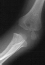

- TREATMENT: The patient was taken to the operating room where under

general anesthesia and tourniquet control the fracture was exposed utilizing

an anterolateral approach, taking care not to disturb the posterior vascular

pedicle of the lateral condyle. Following adequate reduction of the fracture,

2 diverging k-wires were placed across the fracture site.

The

patient was immobilized in a long arm cast at 90 degrees until radiographic

evidence of healing was apparent. The long arm cast and k-wires were removed

in clinic.